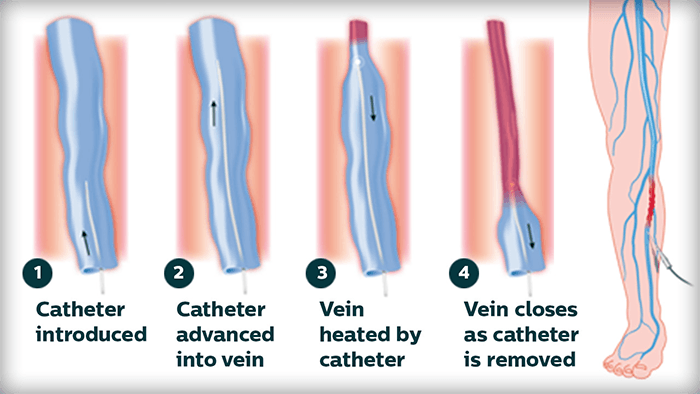

Ablation Therapy

A minimally invasive treatment that uses lasers, radiofrequency, non-thermal ablation or mechanochemical ablation to shut down large varicose veins in the legs.